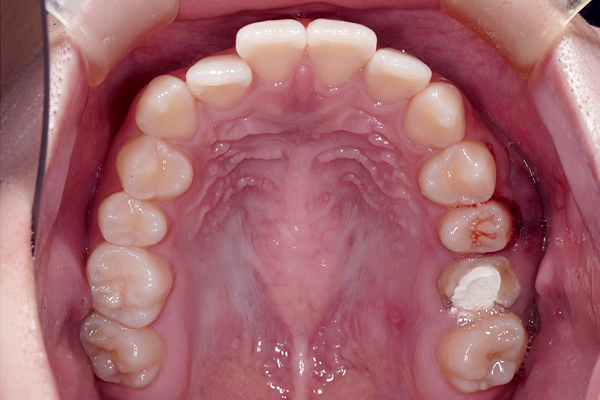

歯槽堤温存術

(リッジプリザベーション)後5ヶ月

インプラント治療後

歯槽堤温存術の症例

抜歯時に歯槽堤温存術(リッジプリザベーション)を行うことが出来たので、インプラント治療時に大きな骨造成を行わなくても治療を行うことが出来ました。治療期間は8ヶ月でした。